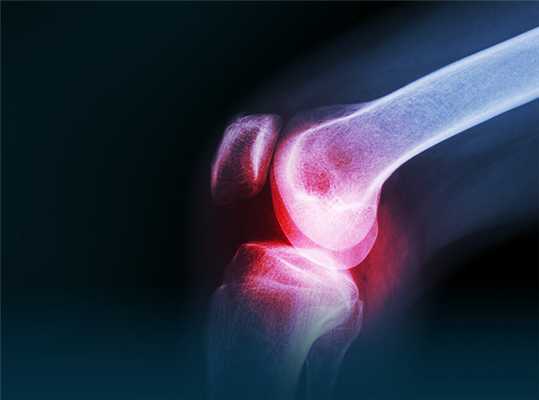

- Рентгенографии. К рентгенологическим критериям ревматоидного артрита относится обнаружение диффузного или пятнистого эпифизарного остеопороза, сужения суставных щелей, краевых эрозий. По показаниям назначается МРТ сустава.

Рентгенография кистей. Поражения суставов при ревматоидном артрите (IV стадия по Штейнброкеру). Костный анкилоз; множественные эрозии суставных поверхностей; подвывих в суставах; остеопороз.